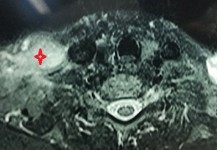

right sciatica nerve after intramuscular injection